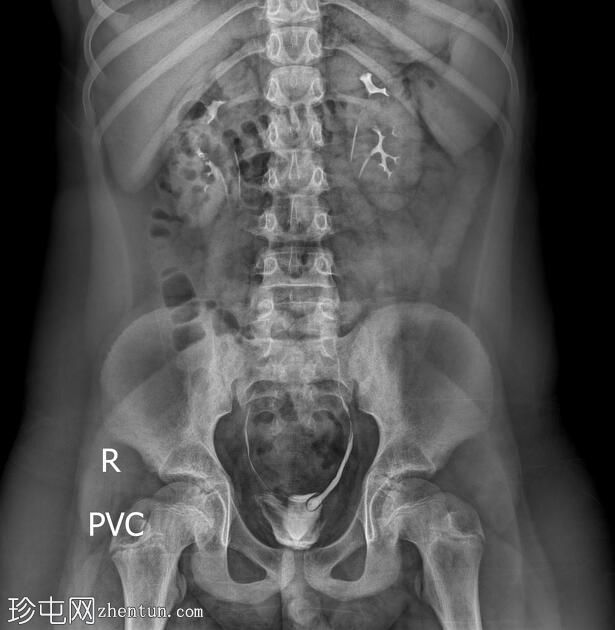

透视检查

正位

双侧肾盂肾盏系统及输尿管重复畸形。

左肾上极异位输尿管末端形成输尿管囊肿。

根据魏格特-迈耶定律,在完全性输尿管重复畸形的双肾病例中,上极和下极分别由独立的输尿管引流。上极输尿管通常存在异位开口,位于下极输尿管的内侧和下方,并常形成输尿管囊肿,正如本病例所示。